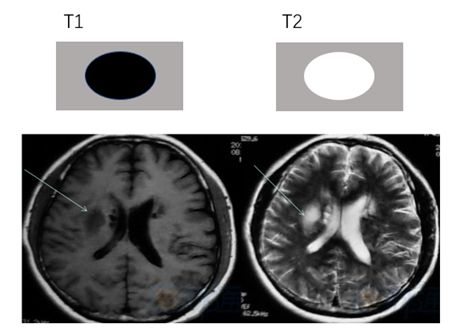

▎急性期:7~24小时至2~3天

急性期红细胞的细胞膜保持完整,细胞内的氧合血红蛋白释放出氧变成脱氧血红蛋白。此期,T1WI上信号变化不明显,T2WI上表现为低信号。血肿周围的水肿在MRI上表现为T1WI低信号,T2WI较高信号。